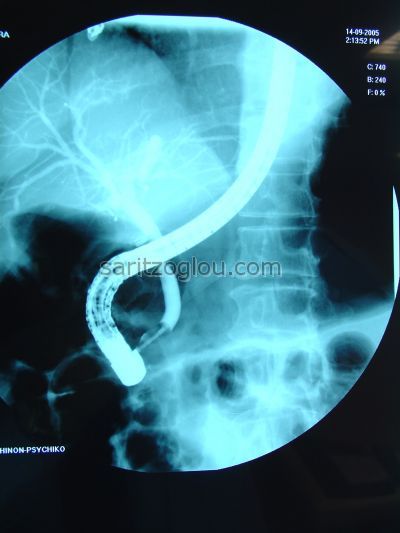

Μεγάλη διάταση του χοληδόχου πόρου λόγω, απόφραξής του, συνεπεία χοληδοχολιθίασης. Απεικονίζεται η παρουσία μεγάλου λίθου.